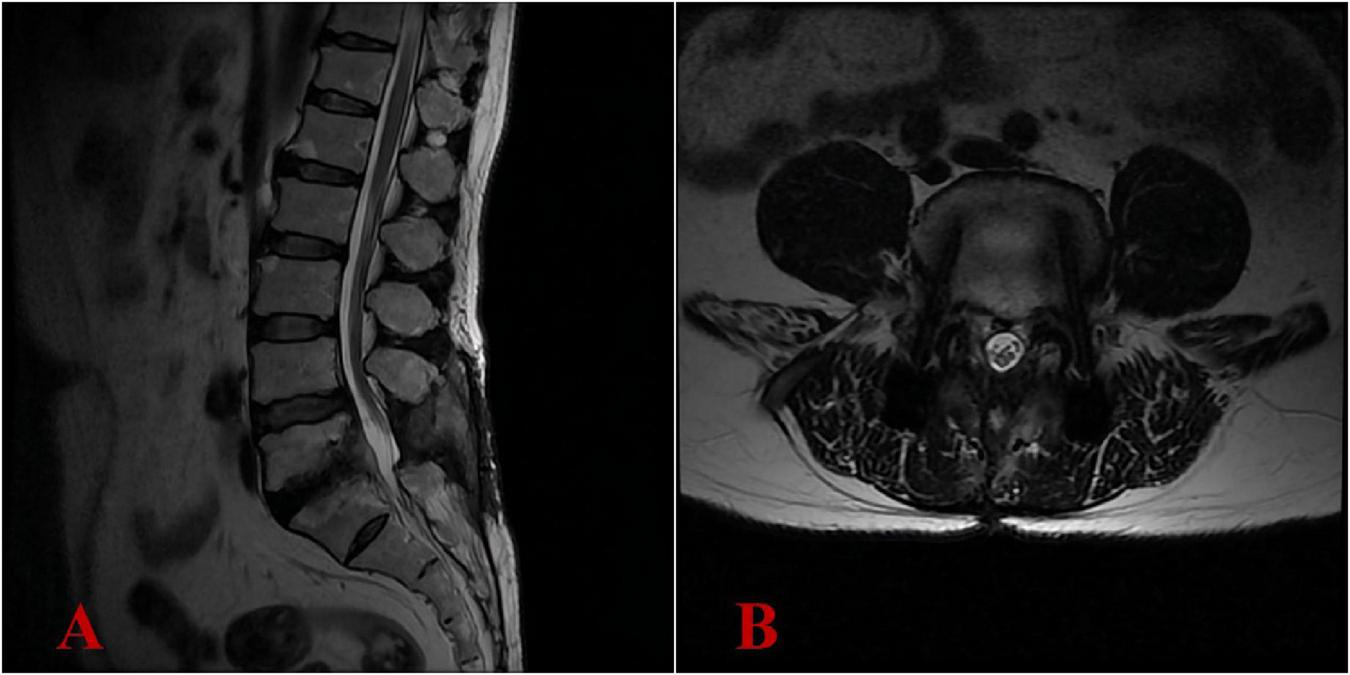

At 3 months postoperatively, the ODI showed significant improvement, scoring 15/100 (mild disability), while the VAS for pain intensity demonstrated minimal residual discomfort at 3/10. Results from complete blood count, liver and kidney function tests, ESR, PCT, and CRP were within normal limits. At 6 months postoperatively, the ODI demonstrated exceptional functional recovery, achieving a score of 10/100 (equivalent to normal function), while the VAS for pain intensity exhibited minimal residual discomfort at 1/10 (nearly pain-free). The patient’s clinical symptoms had completely relieved. The lumbar MRI demonstrated complete resolution of the intraspinal abscess, with no recurrence of infection (Figures 5A, B). The antibiotic regimen of oral doxycycline at 200 mg once daily and ciprofloxacin at 1,000 mg once daily was continued, with the plan to maintain anti-infective treatment until 18 months post-surgery (Supplementary Table 1).

FIGURE 5

Six-month postoperative lumbar MRI demonstrated complete resolution of the intraspinal abscess, with no recurrence of infection. (A) Lateral view; (B) transverse view.